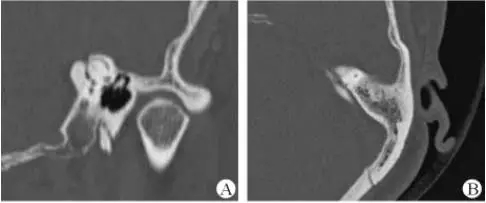

1、上半規管裂綜合征

內耳結構非常微妙。即使是內耳中大頭針樣的孔洞也能造成平衡失調?;颊叱32桓疫M行如走路或轉頭的日常活動。此罕見疾病,醫學專家預估至少影響著人口的1%??稍斐蓯盒?,眩暈以及對噪聲極高的敏感性。病人還常常抱怨他們能聽到血管跳動的聲音。其中一位患者曾告訴耳科專家,他都能聽到自己轉動眼睛的聲音。

診斷及治療

醫生若懷疑此病將會安排內耳CT掃描。在大多數案例中,一旦此病被耳鼻喉科醫生或其它聽力健康專家確診,則可實行手術治療。外科手術風險包含聽力損失以及神經損傷;重建及復原需內耳的治療以及大腦的重塑。

2、膽脂瘤

另一個不常見的疾病叫膽脂瘤,發病率為1/10000,這個“腫瘤”在內耳中逐漸生長。盡管不是惡性的,但也能導致永久性的聽力損失以及其它嚴重的疾病,比如腦膜炎。癥狀是有臭味的耵聹以及聽力損失。